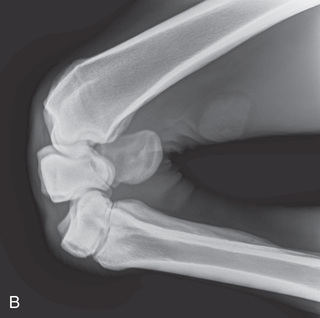

For the dorsolateral-palmaromedial oblique (DLPMO) view (Fig. 24.6B), the central ray faces the dorsal part of the limb aimed 45 degrees laterally from the midline. The image receptor is on the palmaromedial aspect of the limb so that it is perpendicular to the beam. Remember “point of entry to point of exit”; the beam travels from dorsolateral to palmaromedial. The film marker is placed along the lateral aspect of the image receptor. So that there is no confusion as to what angle should be used, the proper description for this 45-degree DLPMO view is dorsoproximal 45-degree lateral palmarodistomedial oblique (DPr45L-PaDiMO).

What is actually being highlighted on this DLPMO projection (Fig. 24.6B) is the portion that is not against the film—specifically the lateral sesamoid in Fig. 24.6B. Note that because this is taken at an oblique angle, the image of the medial proximal sesamoid is obstructed by the distal metacarpus (see Technician Notes). Thus an oblique projection allows the portion of the bone farther from the film to be in profile. The radiograph is like a shadow: the way the beam is directed, the body part on the film is superimposed in the oblique, and the opposite edges are highlighted.

The view is correctly described first from where the beam enters on the limb and then where it exits. Using point of entry to point of exit the DLPMO is technically termed a medial oblique because the beam enters off the midline on the lateral aspect and exits on the medial aspect. The medial aspect is against the film. However, because the lateral portion of the bone is in profile in a DLPMO, practicing veterinarians may refer to the position as a lateral oblique.

The same principle applies to the dorsomedial-palmarolateral oblique (DMPLO) (Fig. 24.6A), but this time the central ray is aimed at the dorsal part of the limb 45 degrees medially to the midline. The image receptor is on the palmarolateral aspect of the limb and is perpendicular to the beam. The beam travels from dorsomedial (point of entry) to palmarolateral (point of exit). The film marker is placed along the lateral aspect of the image receptor, appearing to be on the dorsal part of the limb in the radiograph. So that there is no confusion as to what angle should be used, the proper description for this 45-degree DMPLO is dorsoproximal 45-degree medial–palmarodistolateral oblique (DPr45M-PaDiLO).

Taking the two middle and two outer letters once the “O” is removed tells us that the dorsolateral and mediopalmar surfaces (red lines on Fig. 24.6A) will be highlighted. The medial proximal sesamoid is in profile.

Remember the view is correctly described first from where the beam enters on the limb and then where it exits. Using point of entry to point of exit, the DMPLO is technically termed a lateral oblique since the beam enters off the midline on the medial aspect and exits on the lateral aspect. The lateral aspect is against the film. However, because the medial portion of the bone is in profile in a DMPLO, practicing veterinarians may refer to the position as a medial oblique.

The DLPMO view is used to view the lateral sesamoid (see Fig. 24.6B and Fig. 24.24A-B), and the DMPLO to view the medial sesamoid (see Fig. 24.6A and Fig. 24.24C-D).